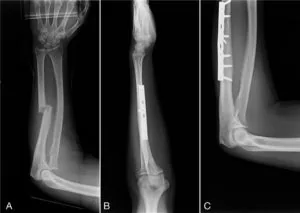

Hand, Wrist & Forearm Fractures

Our Approach: Accurate diagnosis with X-rays or CT scans is critical. Dr. Traverso specializes in both non-surgical and surgical management. Many fractures can be treated with custom casting or splinting. For more complex fractures, Dr. Traverso uses advanced surgical techniques, including plates and screws, to precisely realign the bone and ensure optimal healing and functional recovery.